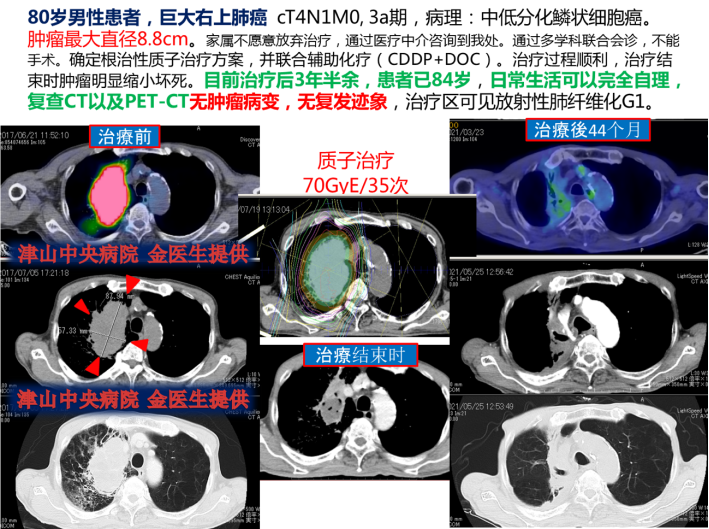

质子/重粒子的实际案例——巨大右上肺癌(中低分化磷状细胞癌)

家属不放弃治疗联系了我们。在日本进行多学科问诊后,无法进行手术,进行根治性放疗(质子)并同步进行辅助化疗。由于患者是高龄我们很担心中途无法坚持,但是这种想法都是多余,原计划顺利结束治疗。后续发给我们复查影响,肿瘤明显缩小并与我们一直保持着联系。